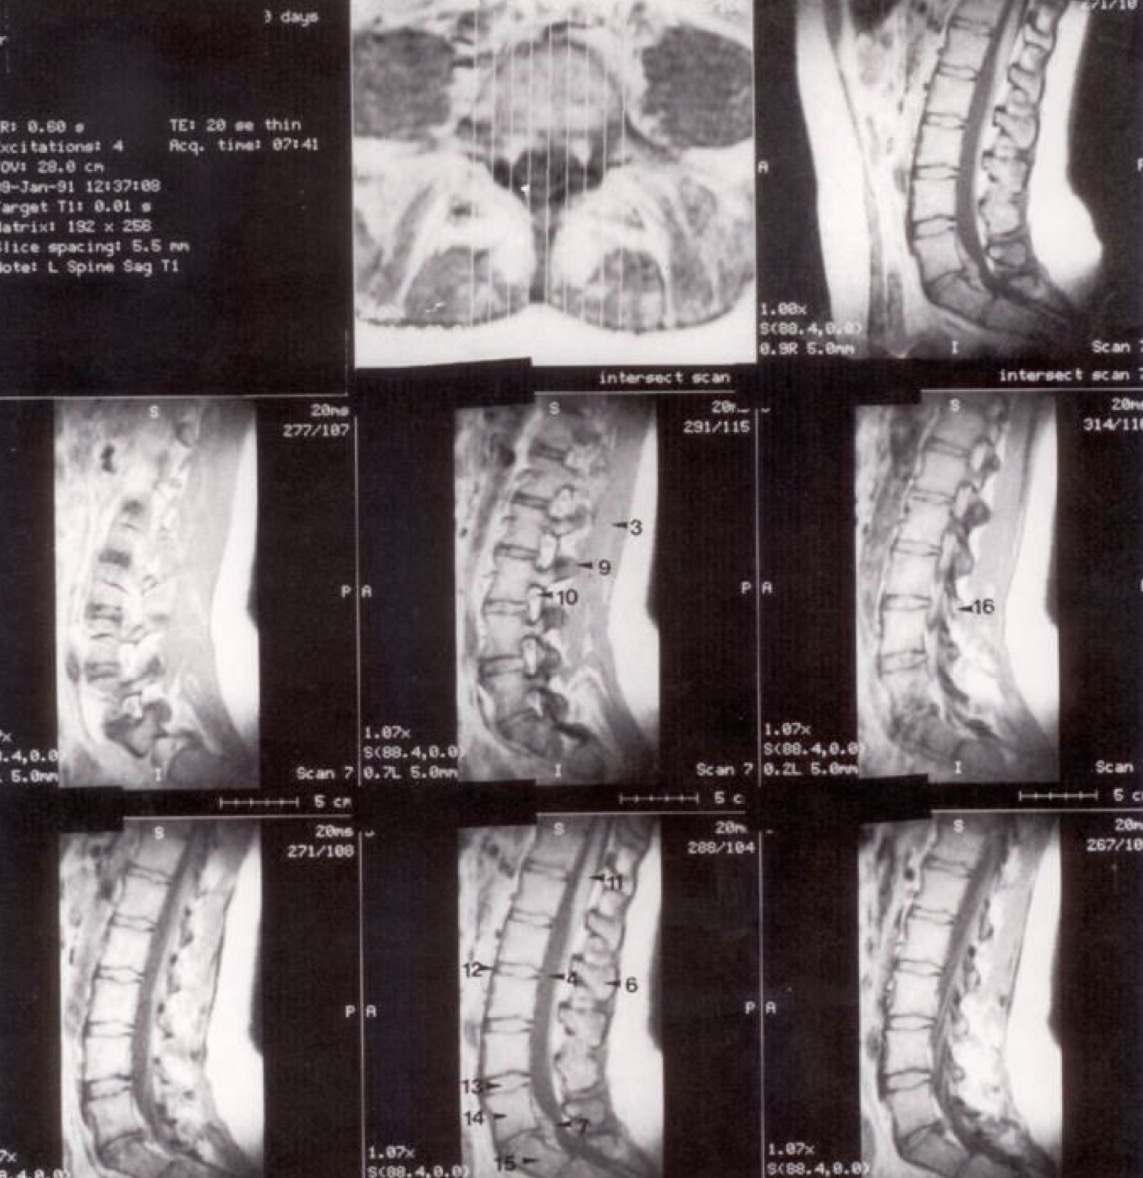

1

M. rectus abdominis (tiesusis pilvo raumuo)

2

M. psoas major (didysis juosmens raumuo)

3

M. erector spinae (nugaros tiesiamasis raumuo)

4

Subarachnoidinė ertmė (spatium subarachnoidale)

5

Ganglion spinale (nugarinis mazgas)

6

Processus spinosus

7

L V - S I disko išvarža (protrūzija/ekstruzija atgal)

8

Tarpslankstelinė anga (tarp L V ir S I dešinėje)

9

Processus articularis superior L III

10

Nervinė šaknelė (radix spinalis)

11

Nugaros smegenys (medulla spinalis)

12

Ligamentum longitudinale anterius (priekinis išilginis raištis)

13

Tarpslankstelinis diskas (tarp L IV ir L V)

14

Corpus vertebrae L V

15

Corpus vertebrae S I

16

Processus articularis inferior L III

Metodika (a)

Horizontalūs (ašiniai) pjūviai per lumbosakralinę dalį. Pirmasis pjūvis yra žemiausias, kiti trys kyla į viršų per L IV - V diską.

Metodika (b)

Sagitaliniai (šoniniai) pjūviai. Vidurinis pjūvis matomas viršutinėje eilėje dešinėje, kiti seka eilės tvarka iš kairės į dešinę.

Klinikinis pastebėjimas

Mažas atstumas tarp stuburo ir priekinės pilvo sienos rodo, kad pacientas yra jaunas ir lieknas (mažai visceralinių riebalų).